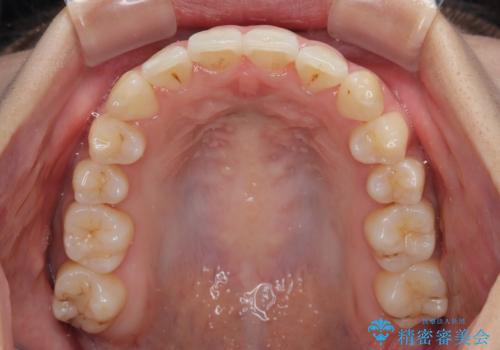

上顎の拡大は、左右どちらに拡大していくのか予想が困難ですが、こちらの患者様では結果として上下正中が一致する方向に拡大され、非常にきれいな仕上がりとなりました。